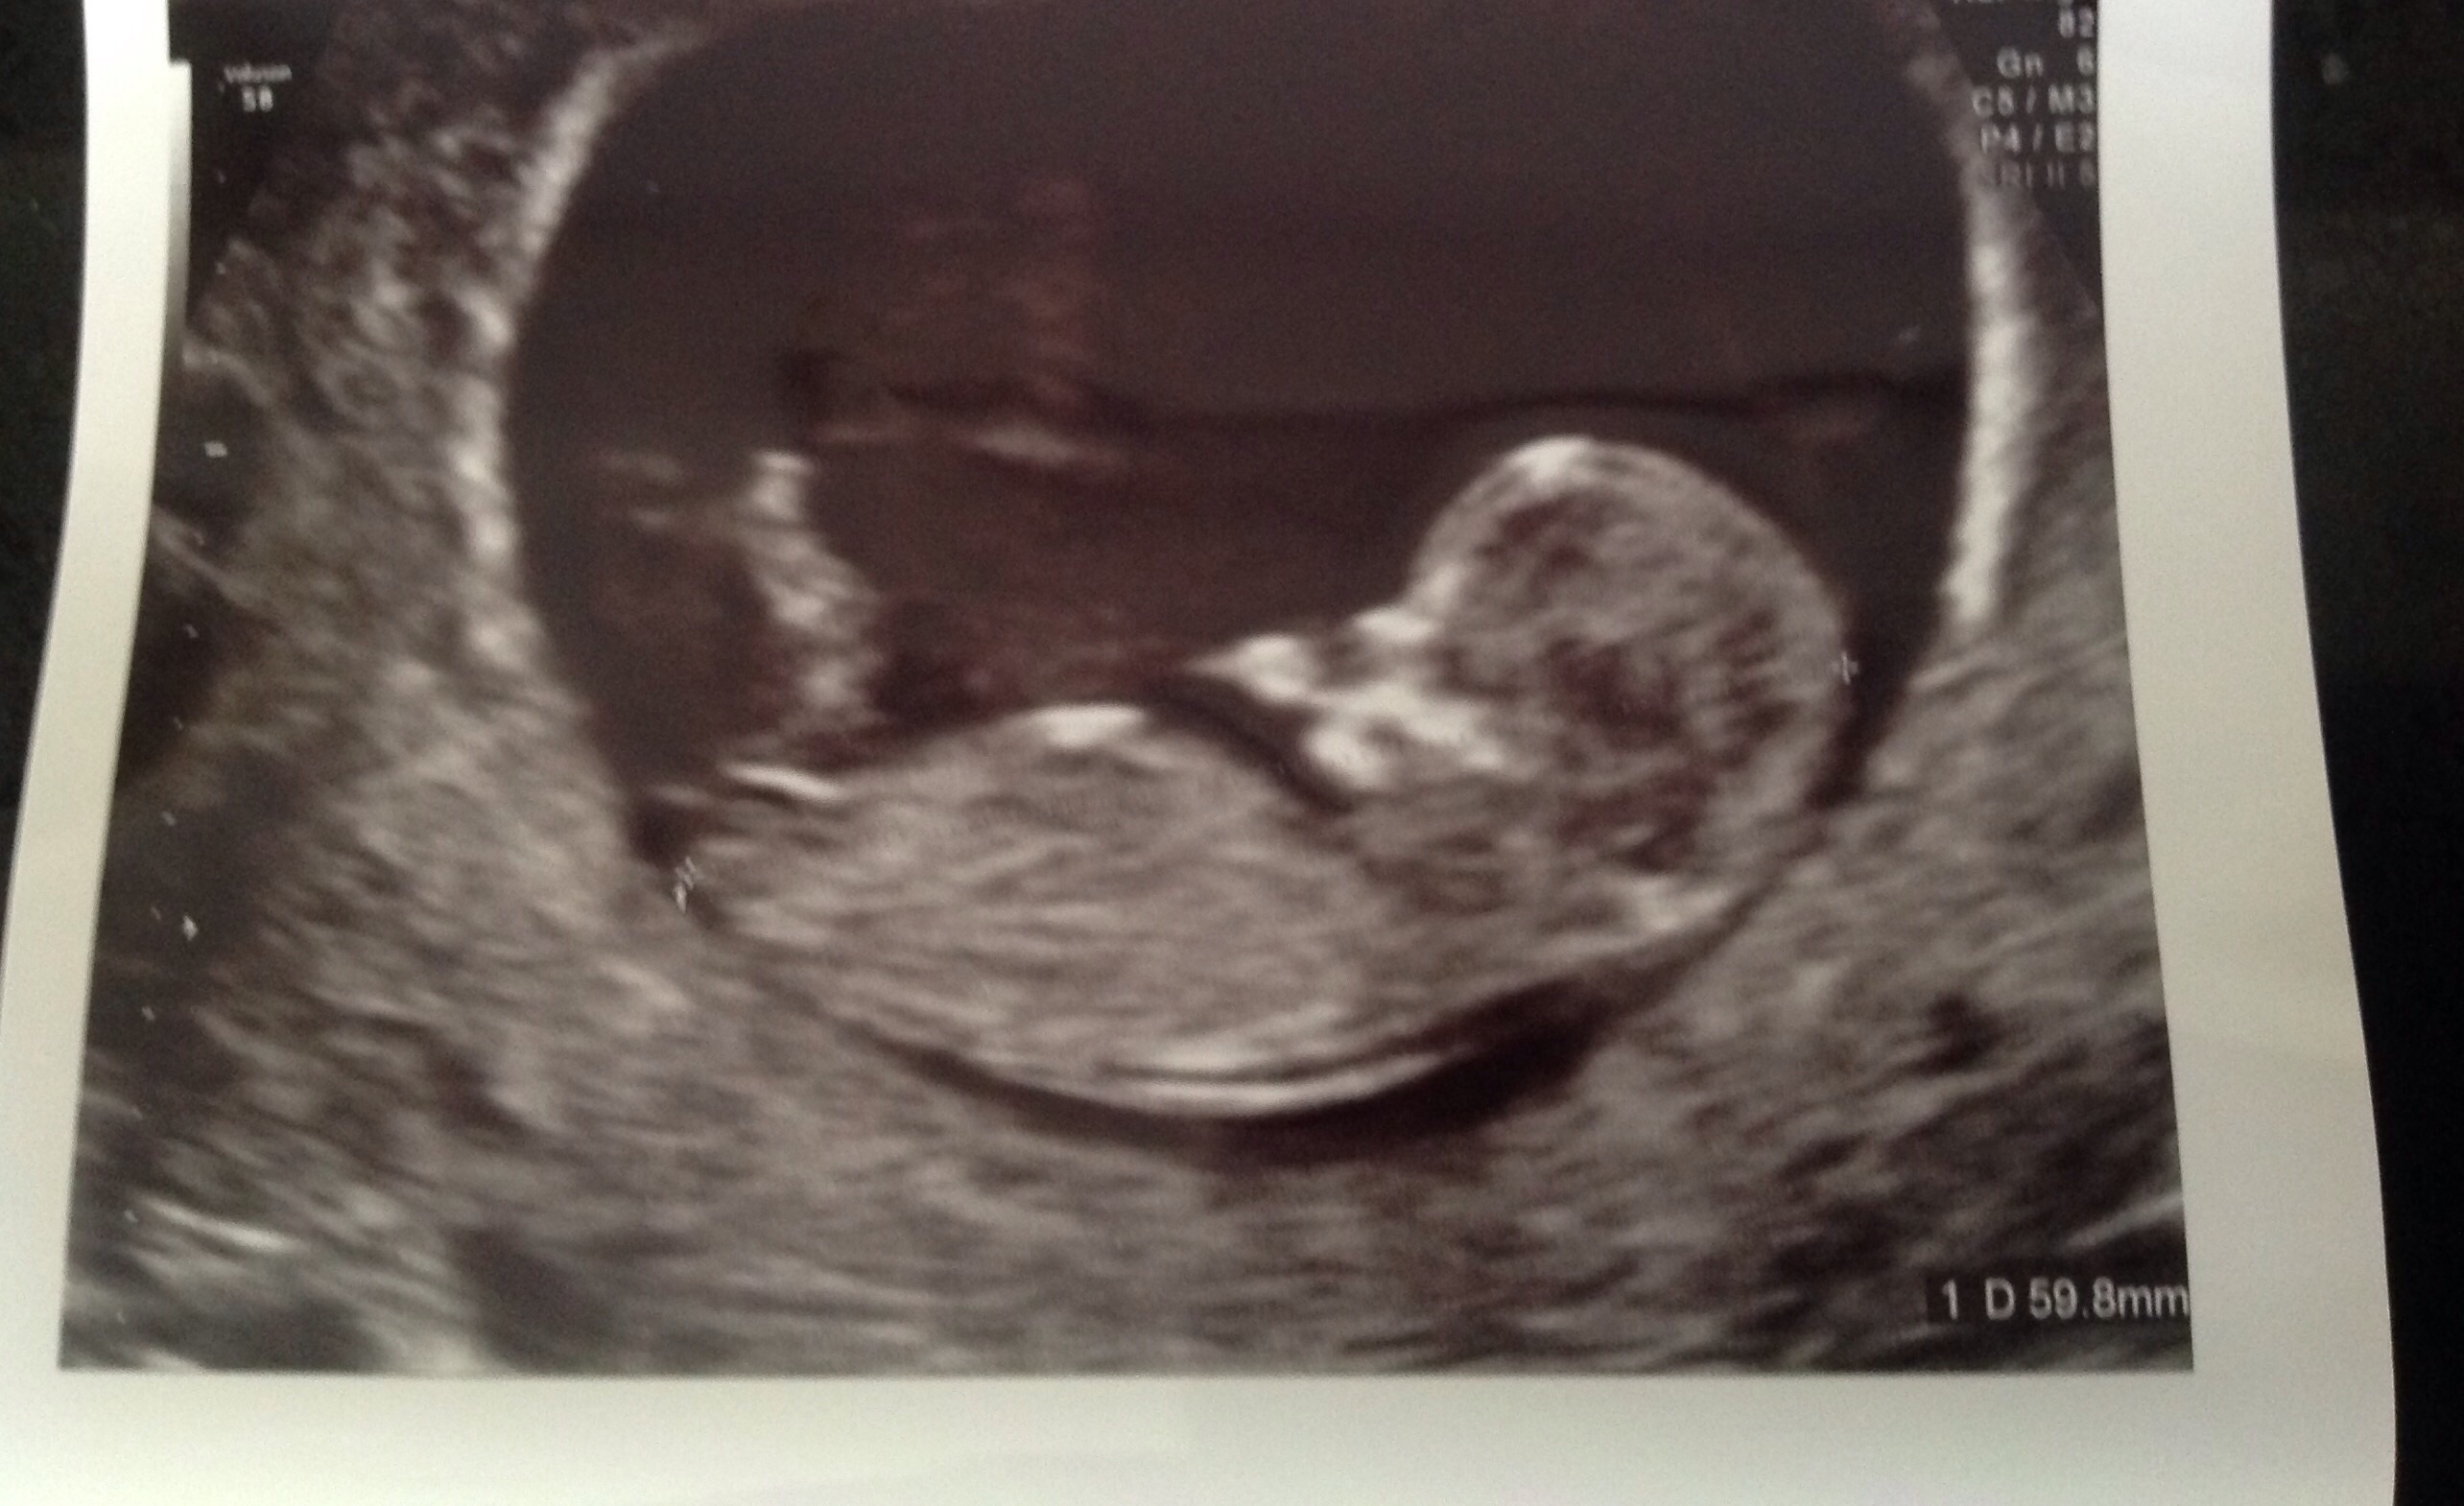

Attachment 29826Hey, I am completely new to the nub theory so was wondering if any experts out there can post me their guess??? It 12+3 gestation Ta

Maybe pink? What is the gestation here?

12+3 thank you for replying

A tad early but I'm still leaning pink. Good luck :happy:

I actually thought boy, just by the angle but obv im not 100%, how long till u find out ?x